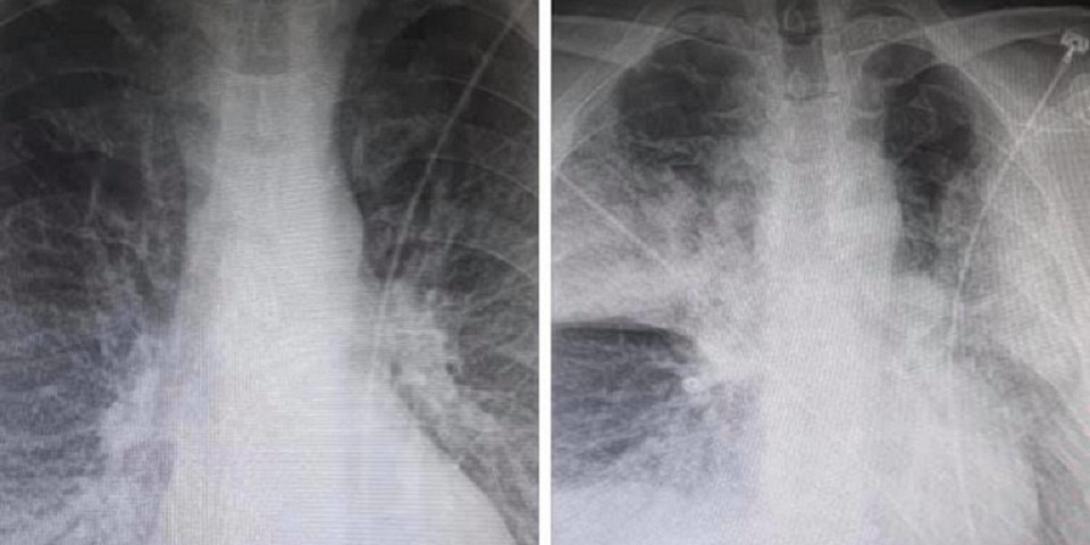

Σοκ προκαλούν οι δύο ακτινογραφίες που ανάρτησε στο Facebook ακτινολόγος από το ΚΑΤ, καθώς αποδεικνύουν την επίδραση που έχει ο κορωνοϊός στους πνεύμονες των ασθενών.

Όπως περιγράφει ο ακτινολόγος του ΚΑΤ Μάνος Καρράς οι δύο ακτινογραφίες ανήκουν σε έναν 38χρονο, ο οποίος είναι καπνιστής και διαβητικός. Σύμφωνα με τον ίδιο, οι ακτινογραφίες έχουν καταγραφεί με 7,5 ώρες διαφορά.

Η πρώτη είναι από την εισαγωγή στις 12 το μεσημέρι με 98% κορεσμό οξυγόνου και η δεύτερη, η επαναληπτική, πραγματοποιήθηκε στις 19:30 με τον ασθενή να είναι πλέον με μάσκα οξυγόνου.

Όπως εξηγεί σε σχόλιο στην ανάρτησή του ο κ. Καρράς, τα «σύννεφα» στη δεύτερη ακτινογραφία συνήθως σημαίνουν υγρό οίδημα φλεγμονή και «είναι κομμάτι του πνεύμονα που "δεν αναπνέει"».

«Δεν υπάρχει ιός» καταλήγει στην ανάρτησή του ο κ. Καρράς απαντώντας σε εκείνους που θεωρούν ότι ο νέος κορωνοϊός δεν είναι υπαρκτός.